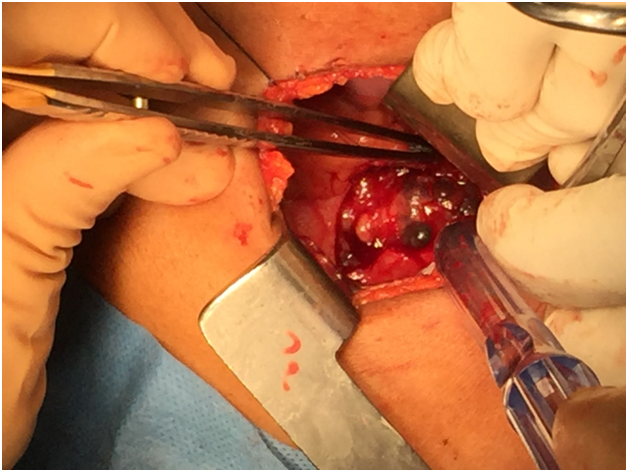

The patient was taken to the operating room where, via a limited right infra-mammary incision and under general anesthesia, pericardial window (Figure 1C) biopsies of the adherent pericardium, the mass invading the right ventricle, and a pulmonary wedge resection of nodules in the right lower lobe were made.

Intraoperatively and grossly, the tumor was noted to be markedly firm and dark red in color. Frozen section of tissue from a lung nodule in the right lower lobe showed a high-grade malignant neoplasm with large pleomorphic cells and frequent mitoses.